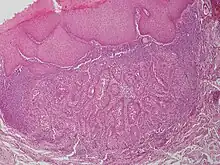

Warty dyskeratoma, also known as an Isolated dyskeratosis follicularis,[1]: 777 is a benign[2] epidermal proliferation with distinctive histologic findings that may mimic invasive squamous cell carcinoma[3] and commonly manifests as an umbilicated (Having a central mark or depression resembling a navel) lesion with a keratotic plug,[4] WD have some histopathologic similarities to viral warts but it's not caused by HPV and the majority of these lesions display overall histopathologic features consistent with a follicular adnexal neoplasm.[5] Usually limited to the head, neck,[6] scalp[7] or face and vulva.[6] Lesions are generally solitary and sporadic and may be associated with a follicular unit. Oral involvement,[4] particularly the hard palate, and genital involvement have been reported. it can also be thought of as one of the manifestations of focal acantholytic dyskeratosis, an epidermal reaction pattern that can be seen in several disorders, including Darier's disease and Grover's disease.[8]: 639 But the main Difference between Darier disease and Warty dyskeratoma, is that Darier disease inherited dermatosis (autosomal dominant) consisting of multiple keratotic papules on the face, trunk, and extremities, while WD occurs as an isolated, noninherited, single keratotic nodule mainly confined to the head and neck as mentioned earlier.[6]